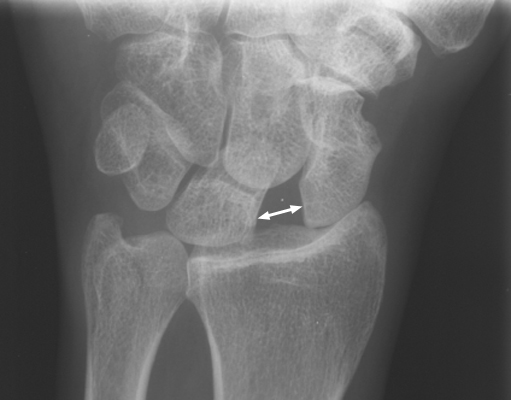

Plain film of the wrist revealing subluxation of the scaphoid bone with obvious widening between the scaphoid and lunate carpal bones. Widening of the joint space between the scaphoid and lunate, seen with rotatory subluxation of the scaphoid (scapholunate dislocation) space is reminiscent of the gap between the teeth of the British comedian Terry Thomas. It has also been called the David Letterman sign or the Lauren Hutton sign (all people with a gap between their two front teeth.) It is an important sign to recognize, since it is a cause of chronic wrist pain and disability if left untreated.

AP wrist - Click on the image for a larger version